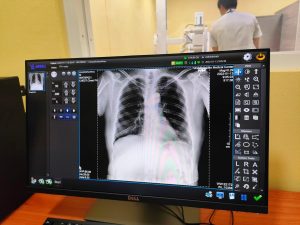

ซึ่งห้องเอกซเรย์ทั่วไป ระบบดิจิตอล ที่ศูนย์แพทย์ชุมชนวัดบางพลีใหญ่กลาง สร้างจนสำเร็จได้ เกิดจากการร่วมไม้ร่วมมือพลังศรัทธาในพระพุทธศาสนาจากประชาชนชาวบางพลี ทั้งจากงานบุญทอดกฐิน และมาร่วมสมทบทุนจากผู้ใจบุญสานฝันพระครูแจ้ จนเป็นจริงรวมเงินทำบุญได้มากถึง สามล้านบาท ทำแบบครบวงจรด้วยนวัตกรรมส่งผลแบบดิจิตอล สามารถประเมินอาการได้อย่างรวดเร็ว ทั้งนี้พระครูแจ้ ได้ทดสอบเครื่องเอกซเรย์ระบบดิจิตอลประเดิมการใช้เครื่องนี้ด้วยตัวเอง ตรวจทั้ง ปอด ไต หัวใจ และก้านคอ ผมออกมาสุขภาพแข็งแรงดี

และในครั้งนี้โรงพยาบาลบางพลีก็ได้รับความเมตตาจากท่านพระครูปลัดสุวัฒนศีลคุณได้เล็งเห็นว่าศูนย์แพทย์ชุมชนวัดบางพลีใหญ่กลางควรเพิ่มศักยภาพการดูแลผู้ป่วย ด้วยการอำนวยความสะดวกให้กับผู้รับบริการที่จำเป็นต้องวินิจฉัยด้วยการตรวจเอกซเรย์ต้องเข้าไปรับการเอกซเรย์ที่โรงพยาบาล ทำให้ไม่ได้รับความสะดวกและใช้เสียเวลาในการเดินทาง จึงได้

บริจาคเครื่องเอกซเรย์ระบบดิจิตอล พร้อมสร้างห้องเอกซเรย์รวมมูลค่ากว่าสามล้านบาท มอบให้ศูนย์แพทย์ชุมชนวัดบางพลีใหญ่กลางในนามของโรงพยาบาลบางพลี ขอกราบขอบพระคุณท่านพระครูปลัดสุวัฒนศีลคุณ แทนประชาชนทุกคนที่ท่านเมตตามอบเครื่องเอกซเรย์ระบบดิจิตอล พร้อมห้องเอกซเรย์ ให้กับศูนย์แพทย์ชุมชนวัดบางพลีใหญ่กลาง